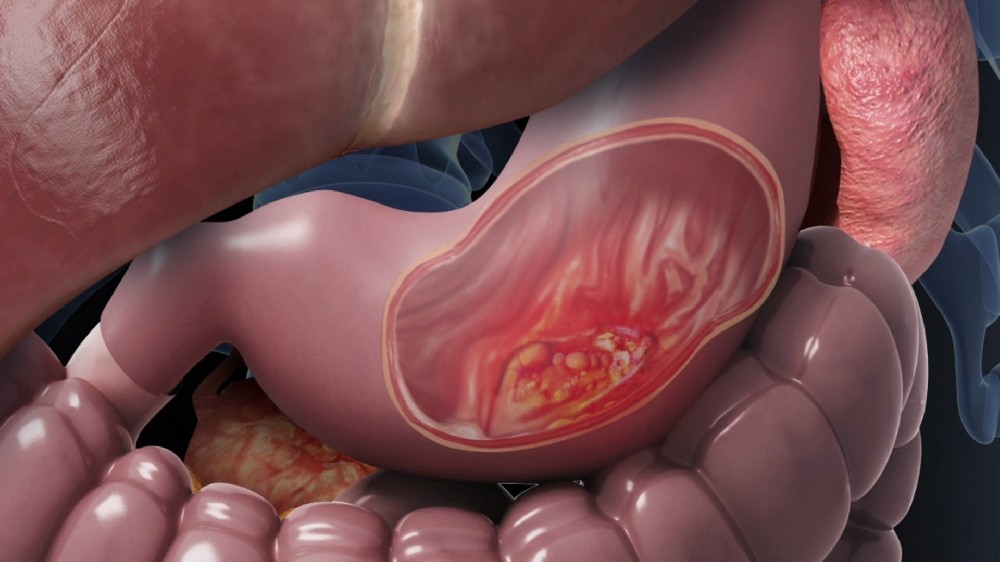

胃癌

4D 的新陳代謝方式 卡路里限制 + 奧米加-3 脂肪酸 我的腫瘤縮小到足以進行手術,而精確的內視鏡黏膜下切除術 ESD 以最小的侵襲移除它。免疫治療 TIM-3 抑制劑 以及有節奏地施用低劑量化療 節拍 防止了復發。我重新開了點心店,並重新享受烹飪的樂趣!

何先生,50歲